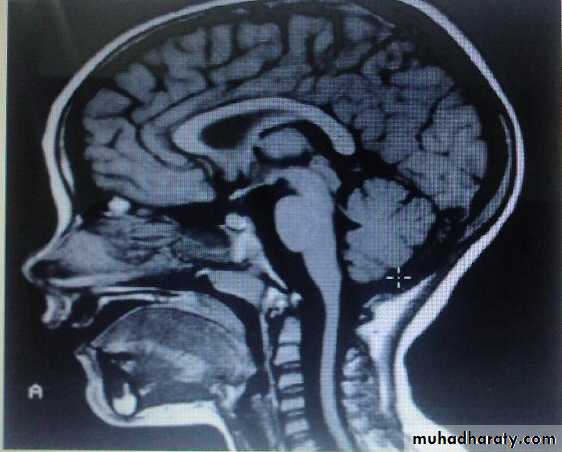

Group of heterogeneous inherited disorders characterized by slowly progressive cerebellar ataxia that affects gait early and severely and may eventually confine the patient to bed. They show considerable clinical variability .Most of them begin in adulthood. Atrophy of the cerebellum and sometimes also of the brainstem may be apparent on CT or MRI scans. Definitive diagnosis is by genetic testing. Treatment is symptomatic.Fridrich Ataxia

Alcoholic cerebellar degeneration

develop in chronic alcoholics lasting 10 or more years, probably as a result of associated nutritional deficiency. most common in men. usually start between 40 and 60 years.Degenerative changes are largely restricted to the superior vermis, usually insidious in onset & gradually progressive over weeks to months eventually reaching a stable level of deficit, Gait ataxia is a universal feature, heel-knee-shin test is +ve in about 80%. CT scan or MRI may show cerebellar atrophy. No specific treatment is available. Abstinence from alcohol, combined with adequate nutrition, leads to stabilization in most cases. All patients with this diagnosis should receive thiamine to prevent development of Wernicke encephalopathy.

Any patient with ataxia should send for :

1-Brain MRI2- CBC and S. B12 LEVEL

3-SPINAL CORD MRI